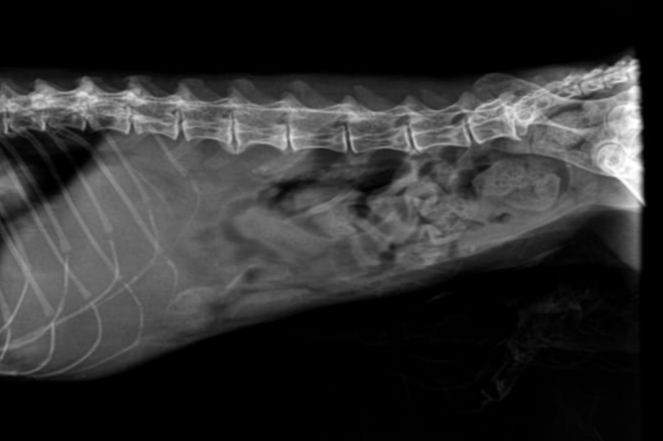

• Abdominal Radiographs: reveal soft-tissue opacity in the cranial abdomen

• Ultrasound: Typically shows a multiloculated cystic hepatic mass with thin septations and fluid-filled cavities; walls are smooth and well-defined.